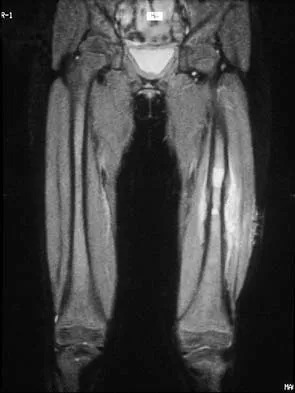

A 16-year-old boy has had thigh pain for the past several months. He denies any history of trauma. Examination reveals a large, deeply fixed, soft-tissue mass in the thigh. Laboratory results show an elevated erythrocyte sedimentation rate (ESR) and leukocytosis. A plain radiograph and MRI scan are shown in Figures 1a and 1b. Biopsy specimens are shown in Figures 1c and 1d. What is the most likely diagnosis?